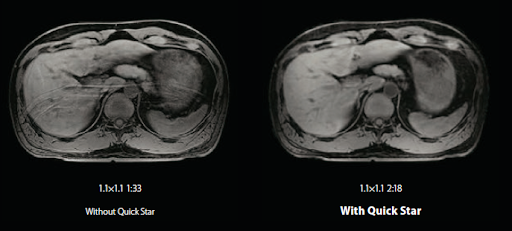

Технология Quick Star

Quick Star снижает количество артефактов из-за движения, что особенно важно для исследования пациентов, которые не могут задержать дыхание и особенно для проведения МРТ-исследования печени.